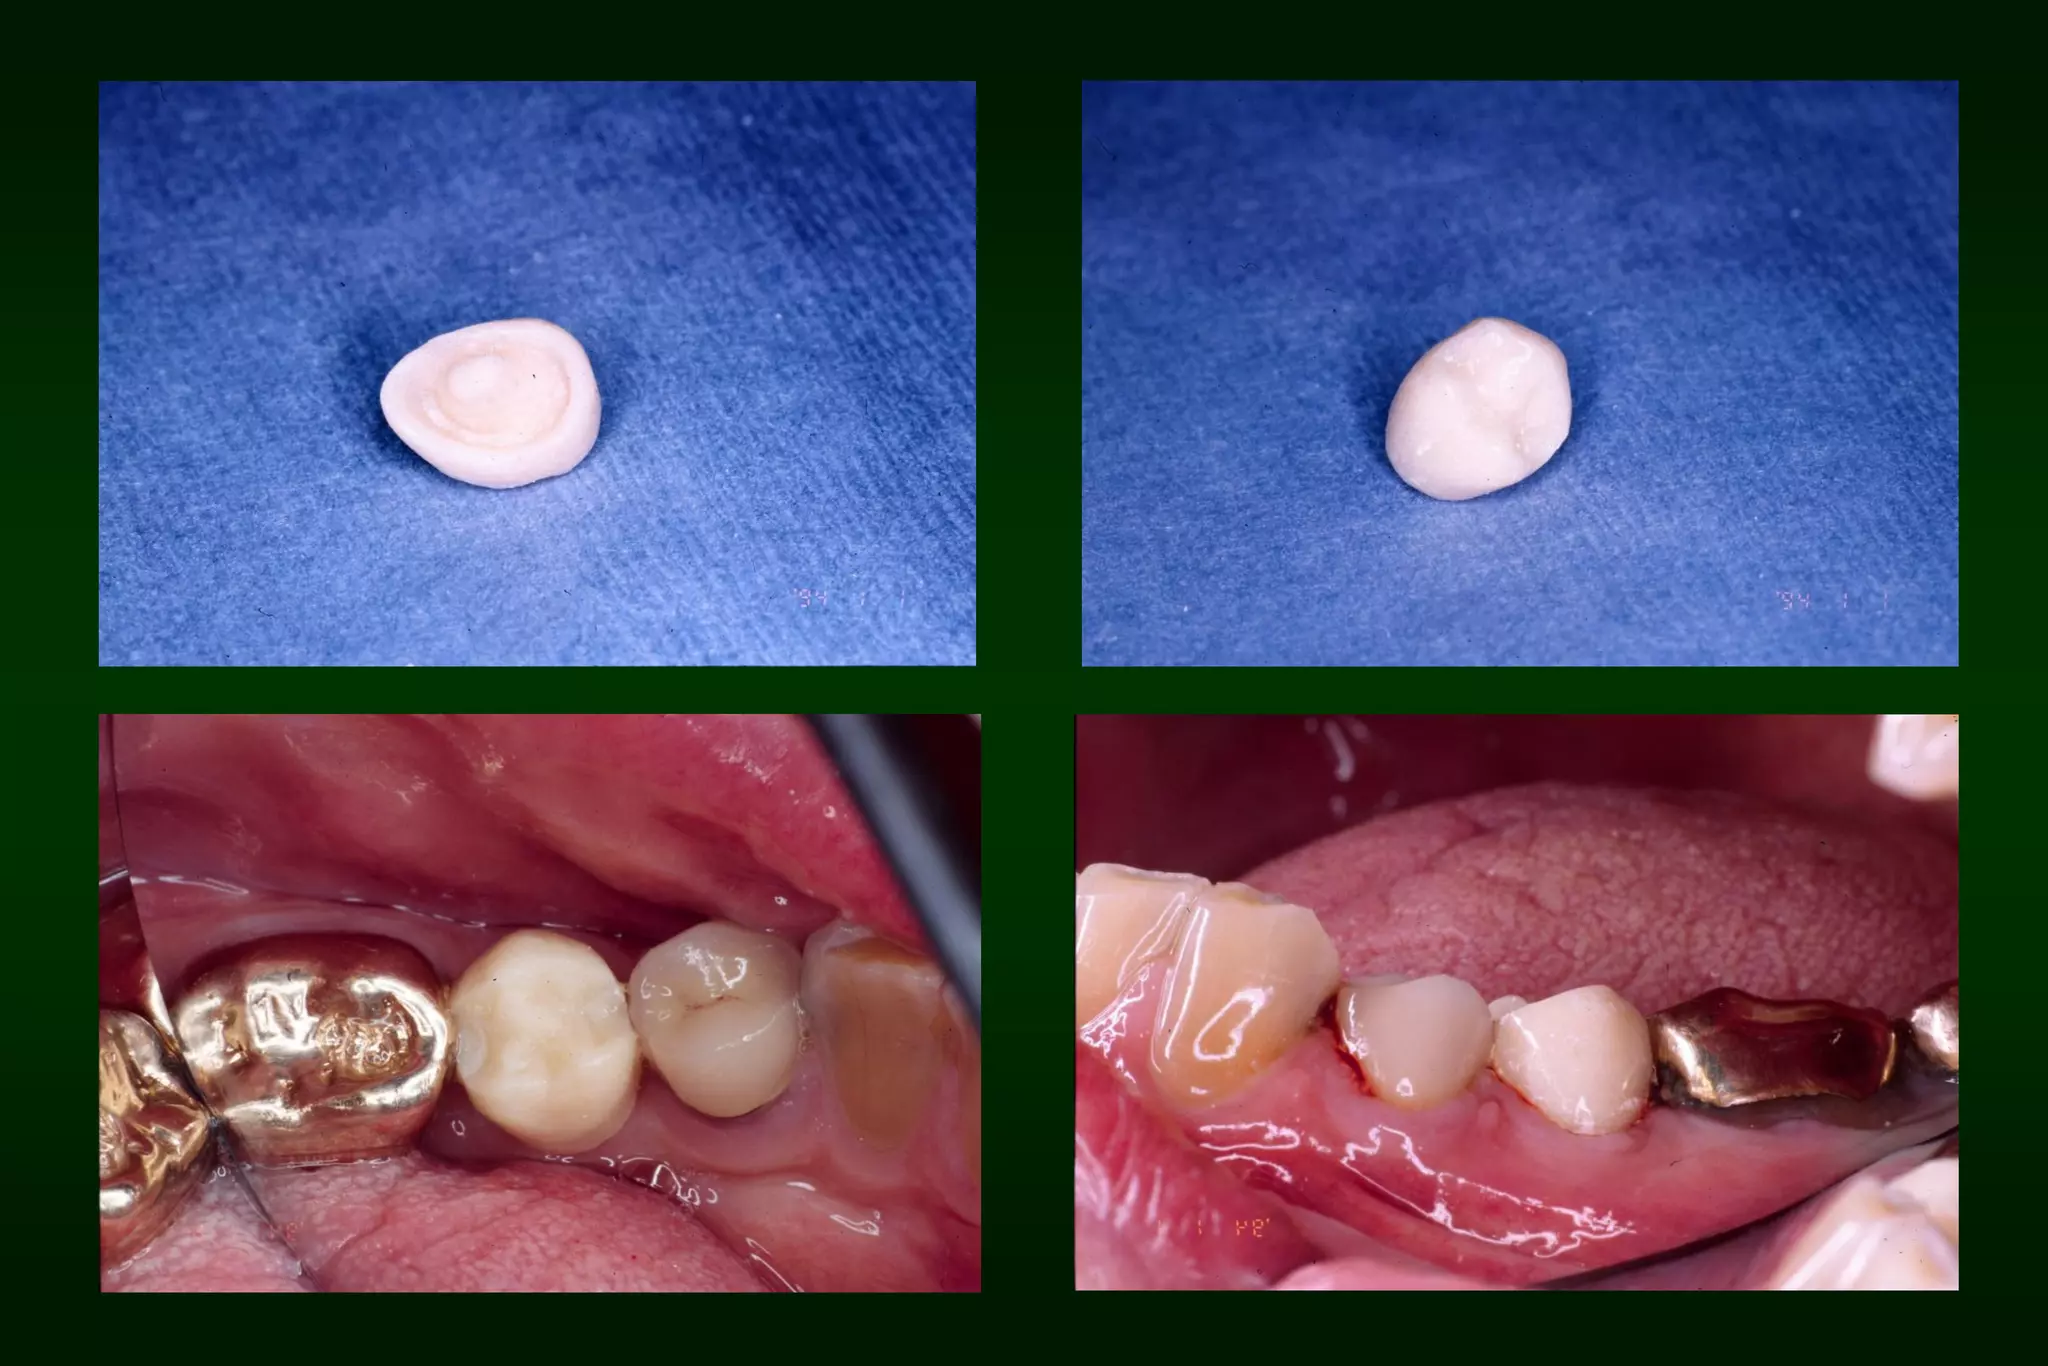

After 1 week

After 2 months

Requirements of Provisional Restoration I. Biologicrequirement: • • • • • Protect the dental pulp Maintain and contribute to the periodontal health Provide comfortable, functional occlusal relationship Maintain tooth position Protect remaining tooth structure